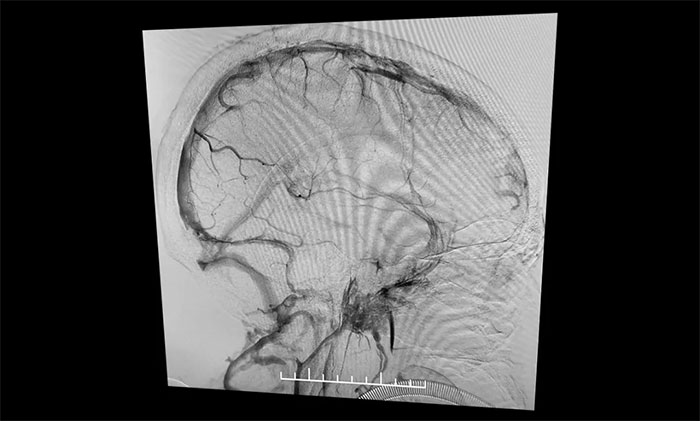

在麻醉科團(tuán)隊(duì)及導(dǎo)管室介入團(tuán)隊(duì)的密切配合和監(jiān)護(hù)下,4A腦血管病一科主任席剛明教授、4A腦血管病一科副主任王貴平博士小心探索,一邊“疏通”,一邊不斷切換正位及側(cè)位造影,避免造成額外損傷。經(jīng)過3個(gè)多小時(shí)的連續(xù)奮戰(zhàn),經(jīng)多次支架取栓、導(dǎo)管抽吸,取出大量暗紅色血栓,復(fù)查造影見上矢狀竇顯影明顯改善,竇匯、右側(cè)橫竇、乙狀竇顯影改善,左橫竇、乙狀竇顯影可,患者顱內(nèi)靜脈竇順利再通。行XperCT未見顱內(nèi)出血。